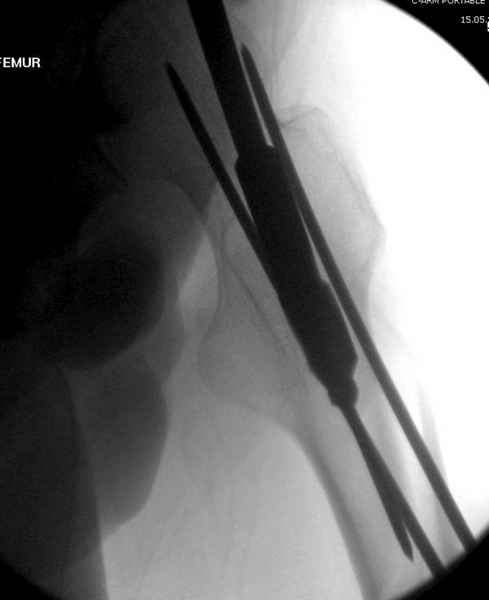

Учитывая, что случай ургентный, больной поступил вечером, не стали делать вытяжение и срочно провели операцию по фиксации перелома бедра антеградным штифтом Versa Nail от DePuy.

Для профилактики дальнейшего раскола в шейке предварительно во время проксимального рассверливания спереди и сзади провели временные спицы, которые в дальнейшем были заменены на шурупы (miss nail method)

Обычная спасательная фасциотомия для обычного больного в этом случае было бы приговором, поэтому несмотря на высокие цифры компартментального мониторинга больного оставили под наблюдением с обкладкой конечности льдом.

Кровотечение удалось контролировать, и больной через пару дней выписан на амбулаторное лечение.